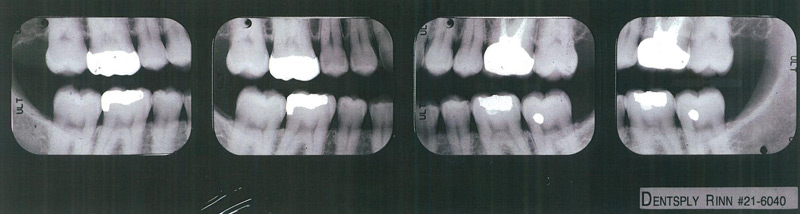

Vertical Bitewings

Vertical bitewings are films that show both upper and lower teeth, but the view extends farther down the root, generally giving an excellent image of the bone. Normally 4-7 views are taken. In cases of severe bone breakdown the film will not show all the bone, and root canal lesions also do not show. They are taken in place of traditional bitewings.